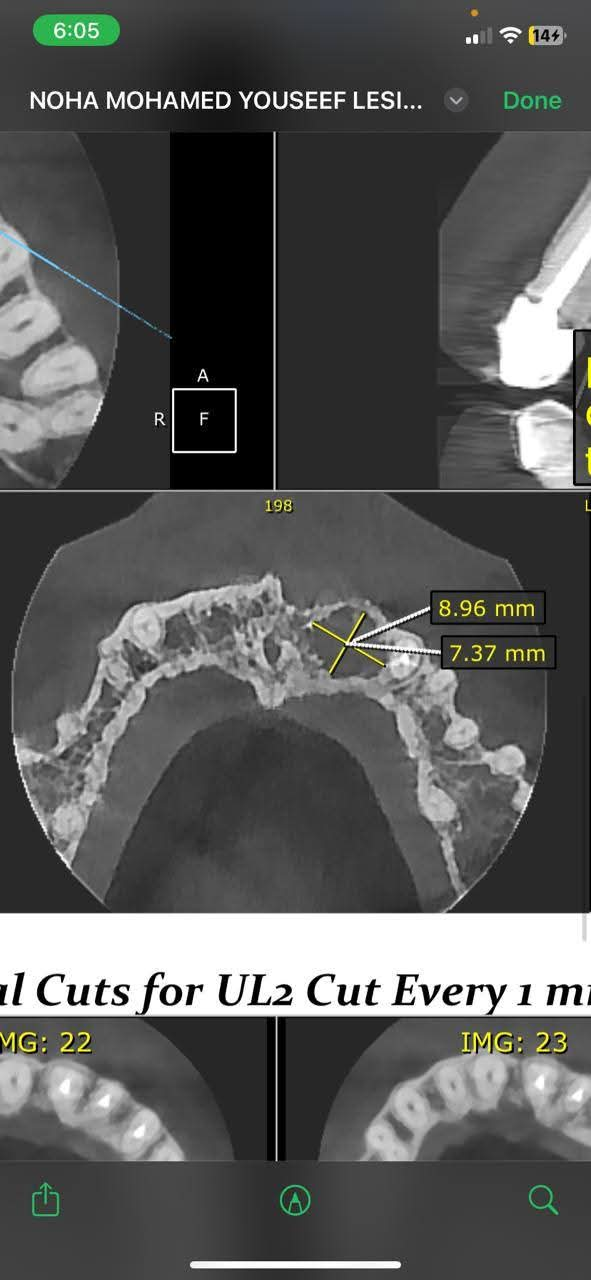

أعلنت مديرية الشؤون الصحية بسوهاج نجاح فريق متميز من أطباء الأسنان بمستشفى جهينة المركزي في إجراء عملية دقيقة لإزالة كيس مرضي تحت القاطع الأول والثاني يسار الفك العلوي لفتاة تبلغ من العمر 23 عامًا.

و استغرقت الجراحة نحو ساعة ونصف تحت التخدير الموضعي، وتمت بنجاح تام مع استئصال الكيس المرضي كاملًا، في سابقة تُعد الأولى من نوعها داخل المستشفى.